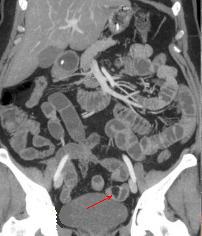

Petit lipome de

l'intestin ( fleche rouge ) . Aspect TDM

arrondie pedicule a hypo-dense endoluminale de

intestin a la region fosse iliaque gauche |